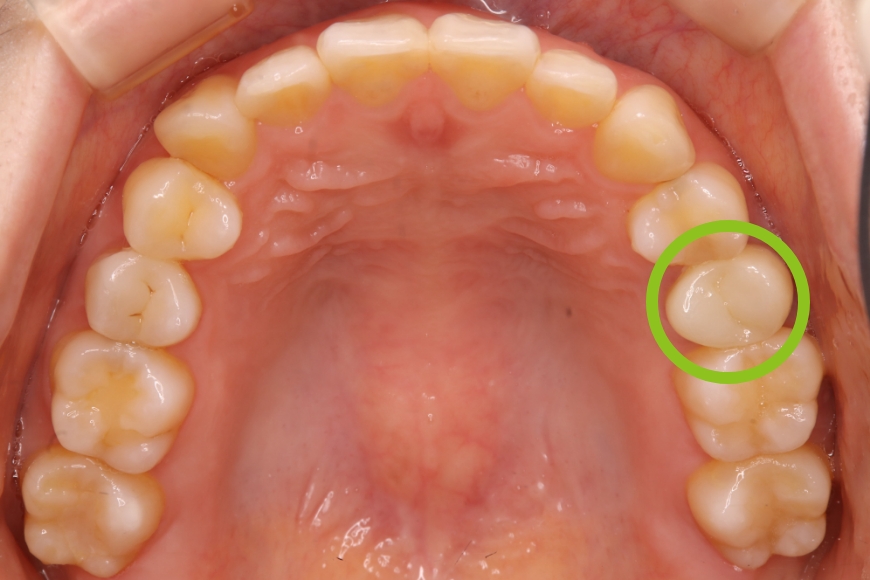

20代女性 上の奥歯へのジルコニア治療およびメタルタトゥーの除去

治療内容 奥歯の被せものをやり直したい、また、歯ぐきが黒くて気になるとのことで来院されました。

金属の被せの表面にプラスチックが張り付けてあり、また、使用している金属が溶け出し、歯ぐきが黒くなっていました(メタルタトゥー)。

装着してある全ての金属を除去後、歯ぐきのメタルタトゥーにレーザー照射を行い、健康なピンク色の歯ぐきを回復しました。その後、審美的および耐久性に優れるジルコニアの被せものを装着しました。

治療後は金属アレルギーのリスクがゼロとなり、メタルタトゥーが起こる心配もありません。

治療期間・回数 治療期間:約3ヶ月程度

通院回数:5回程度

治療費用(総額)

132,000

( ジルコニア 110,000円、メタルタトゥー除去1か所 22,000円。時期や手法により異なる場合があります。)